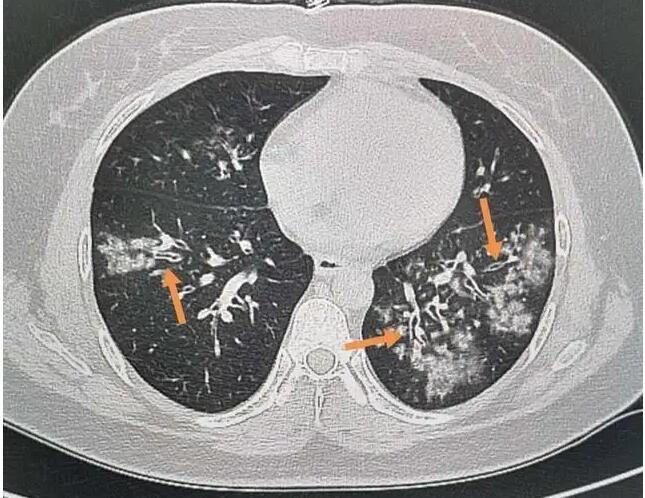

肺炎支原体是一种介于细菌和病毒之间的微生物,也是儿童社区获得性肺炎的常见致病菌之一。它最 “狡猾” 的地方在于症状隐匿、发病缓慢:感染初期多表现为刺激性干咳、低烧(37.5-38.5℃),无明显咳痰,与普通感冒症状高度相似,容易让家长误判为 “普通着凉”。但随着病情发展(通常 1-2 周),咳嗽会逐渐加重,呈现阵发性剧烈干咳,尤其在夜间更为明显,严重时可能影响睡眠;部分孩子会出现高烧不退、呼吸急促、喘息等症状,此时肺部可能已出现炎症浸润,若不及时治疗,可能引发胸腔积液、肺不张等并发症。

治疗方面,若孩子出现持续干咳、低烧超过 1 周无好转,需及时就医,通过支原体抗体检测(IgM 阳性提示近期感染)、胸片等检查明确诊断。确诊后,医生通常会选用大环内酯类抗生素(如阿奇霉素、红霉素)进行治疗,这类药物是治疗支原体感染的一线药物,需严格遵循医嘱按疗程服用(通常为 3-5 天一个疗程,根据病情调整),不可自行停药或减剂量。同时,针对咳嗽、发烧等症状,可配合止咳化痰药、退烧药对症处理,缓解孩子不适。